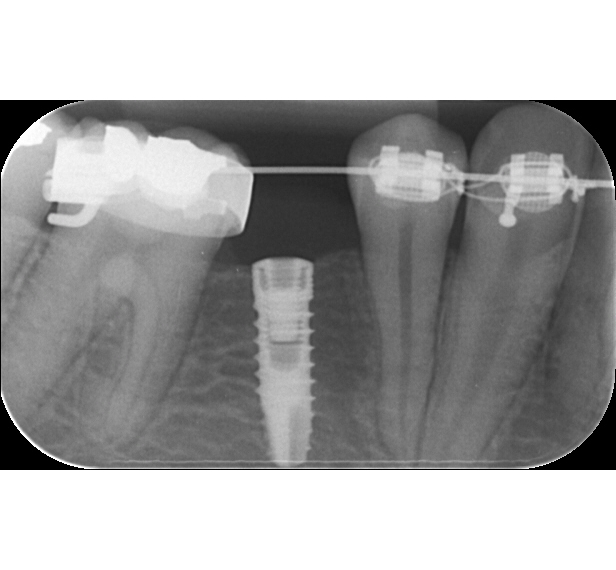

- zavádění válcovách implantátů

- zavádění miniimplantátů

- zavádění kotevních implantátů

Své uplatnění nalezne bezesporu v endodoncii, tedy ošetření kořenových kanálků zubů – možnost přesného zhodnocení jejich průběhu a množství a tím pádem možnost následného kvalitnějšího ošetření, nebo v implantologii – zhodnocení množství a denzity(kvality) kosti, před zavedením kostního implantátu, a tím pádem precizní možnost volby velikosti Vašeho implantátu. Zapomenou nesmíme ani na možnost zhodnocení průběhu důležitých anatomických struktur před extrakcí zejména dolních třetích molárů – zubů moudrosti či v jiných specifických případech.